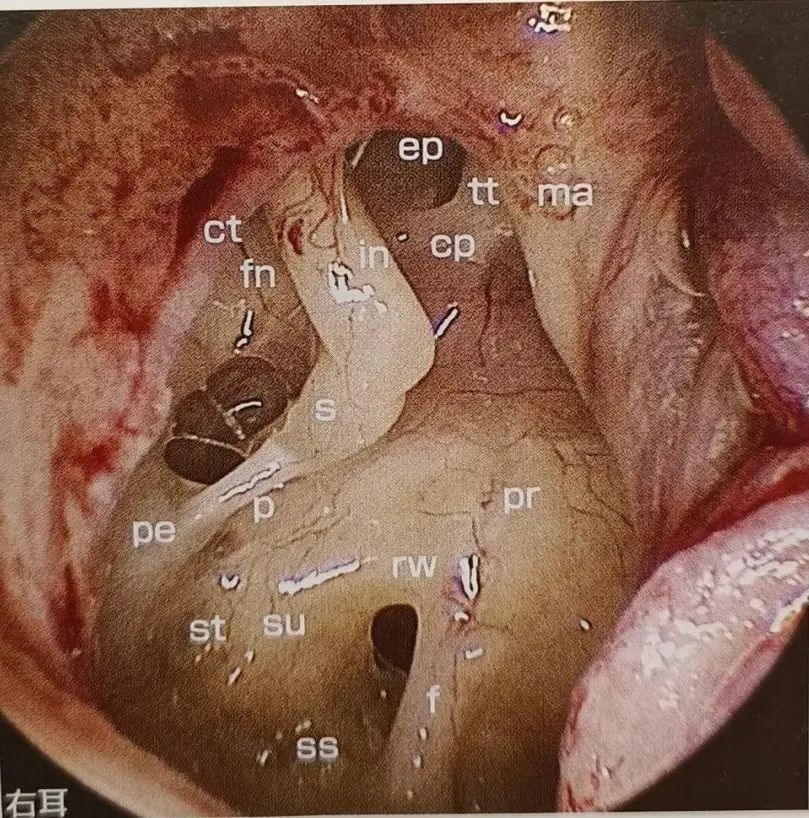

鼓室全貌(右耳)

鼓室内含3块听小骨——锤骨、砧骨、镫骨。

3块听小骨相连接形成听骨链,两端分别连接鼓膜与前庭窗。鼓室周围有6个壁: